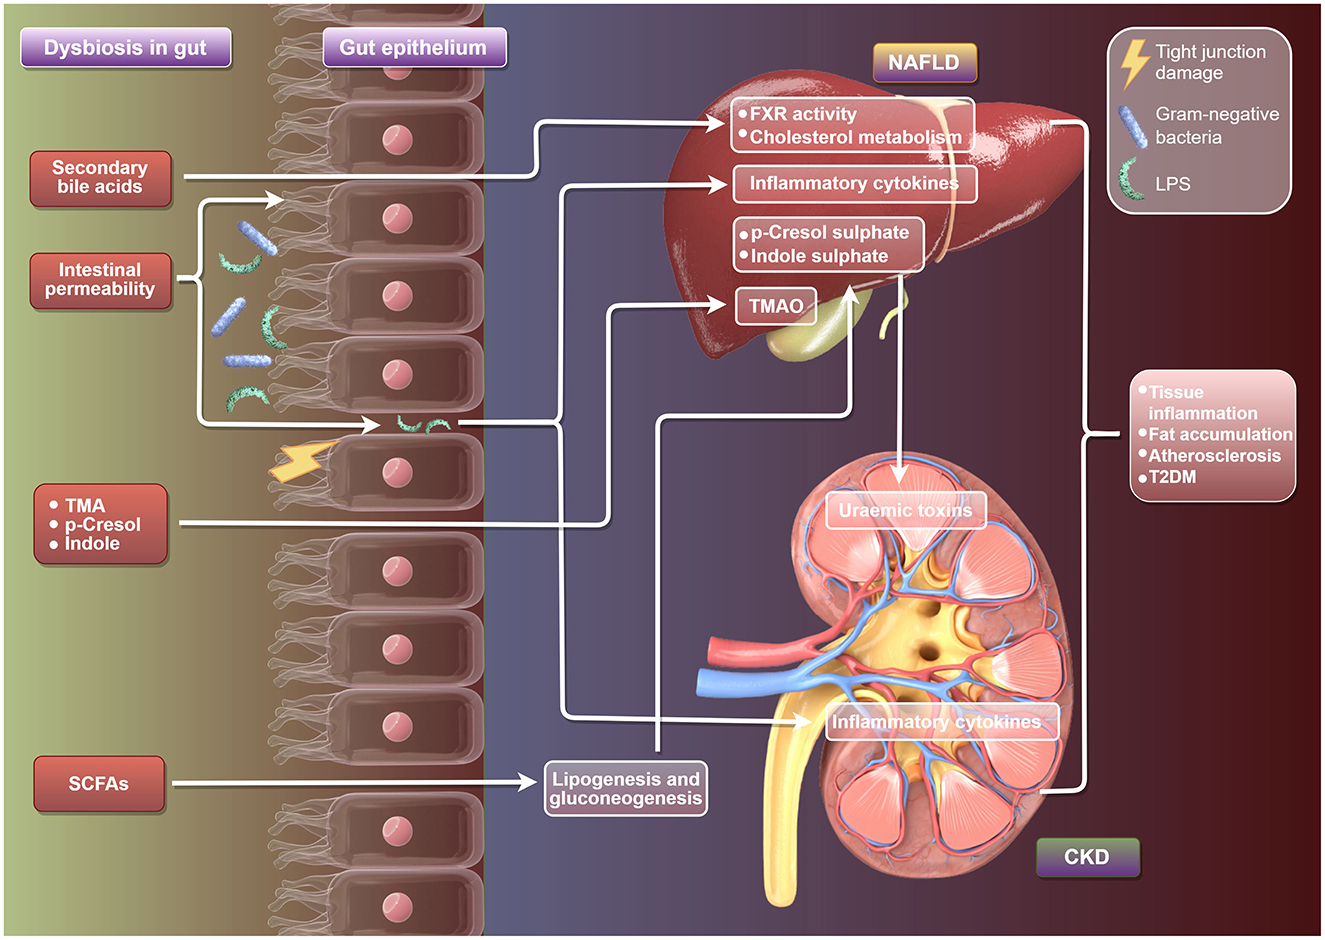

Frontiers | Upper Gastrointestinal Tract IrAEs: A Case。Frontiers | Prevention and treatment of rheumatoid arthritis。Frontiers | Gut microbiota and the “gut-liver-kidney axis。